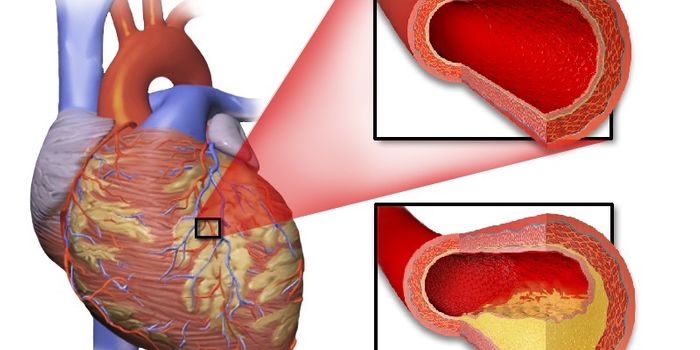

AUG 13, 2017Health & MedicineScientists are illustrating the power of a low coronary artery calcium (CAC) score in the context of heart disease in a ...

JUL 14, 2016CardiologyPeople with type 2 diabetes are more than twice as likely as people without diabetes to develop coronary artery disease. ...